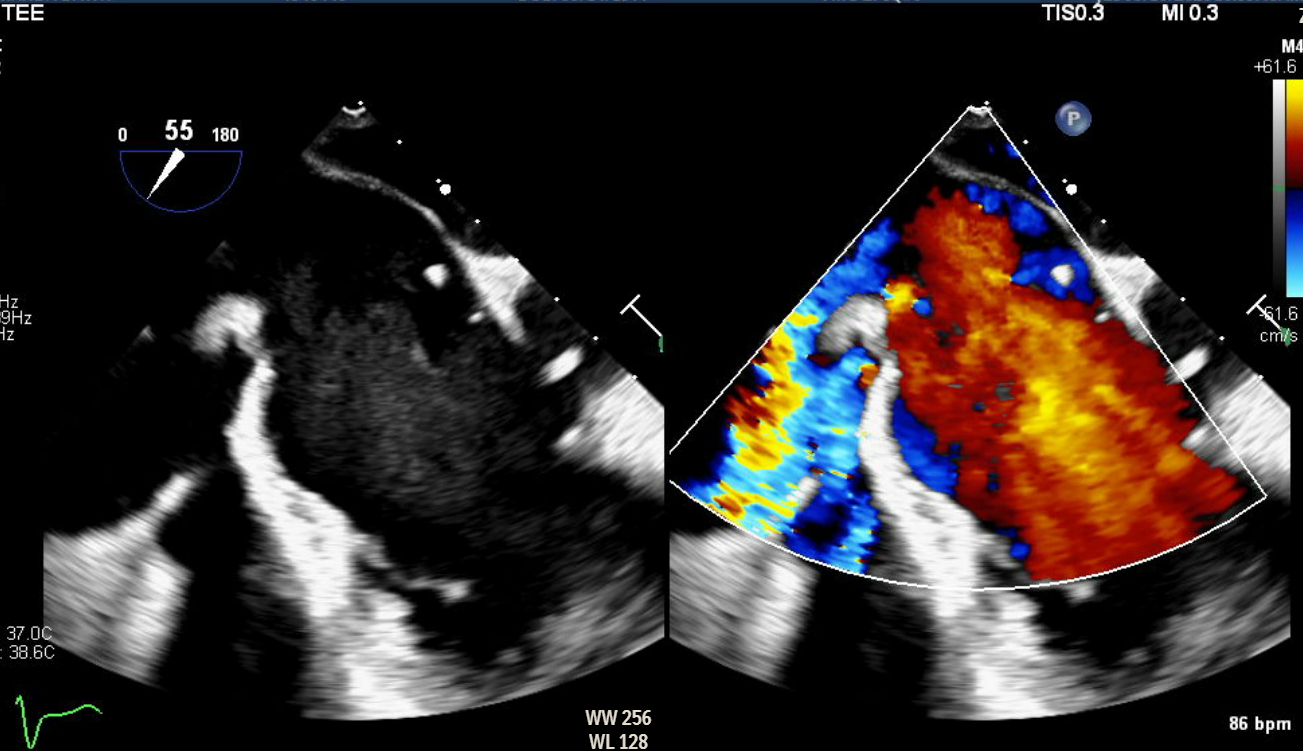

Abstract Body (Do not enter title and authors here): Here is a rare and diagnostically challenging case of infective endocarditis (IE) involving the Chiari network in a 47-year-old female with a complex cardiac and social history. She had a history of intravenous drug use (IVDU), prior methicillin-sensitive Staphylococcus aureus (MSSA) bacteremia involving the mitral valve (MV), and methicillin-resistant Staphylococcus aureus (MRSA) endocarditis requiring tricuspid valve (TV) replacement with a CorMatrix bioprosthesis. She presented with a 3-day history of fever, progressive right groin pain and swelling, and worsening dyspnea. On admission, she was afebrile but hypotensive and had tachycardia. On examination, she had a loud holosystolic murmur in the left lower sternal border, a pulsatile right groin mass with a bruit, alongside multiple healed track marks on her lower extremities. Blood work was notable for leukocytosis. Computed tomography of the chest, abdomen, and pelvis revealed multiple pulmonary septic emboli and a right femoral artery pseudoaneurysm with an arteriovenous fistula confirmed on duplex ultrasound. Transthoracic echocardiogram (TTE) showed preserved ejection fraction (60-65%), normal aortic and mitral valves, but poor visualization of the prosthetic tricuspid valve. Blood cultures grew MRSA, and the patient was started on IV vancomycin. Transesophageal echocardiogram (TEE) revealed a large, mobile echogenic mass attached to the Chiari network (CN), positioned in line with the tricuspid regurgitant jet. These new findings, absent on prior imaging, strongly suggested isolated Chiari network endocarditis (CNE)

Right-sided infective endocarditis (IE) is a rare clinical entity, accounting for less than 10% of all IE cases. Among these, involvement of the CN- the embryonic remnant of the right valve of the sinus venosus and present in under 2% of the population- is even rarer, with only a few reported cases to date. IVDU remains the leading risk factor for right-sided IE, as seen in our patient. The true incidence of CNE is likely underreported due to the limited sensitivity of TTE, which can make visualizing it challenging. TEE remains the imaging modality of choice for identifying such atypical presentations.

Our case reinforced the critical role of TEE in identifying uncommon, non-valvular sources of infection. In the absence of clear treatment guidelines and high surgical risk, the patient was treated conservatively with a 6-week course of antibiotics followed by repeat TEE for monitoring.